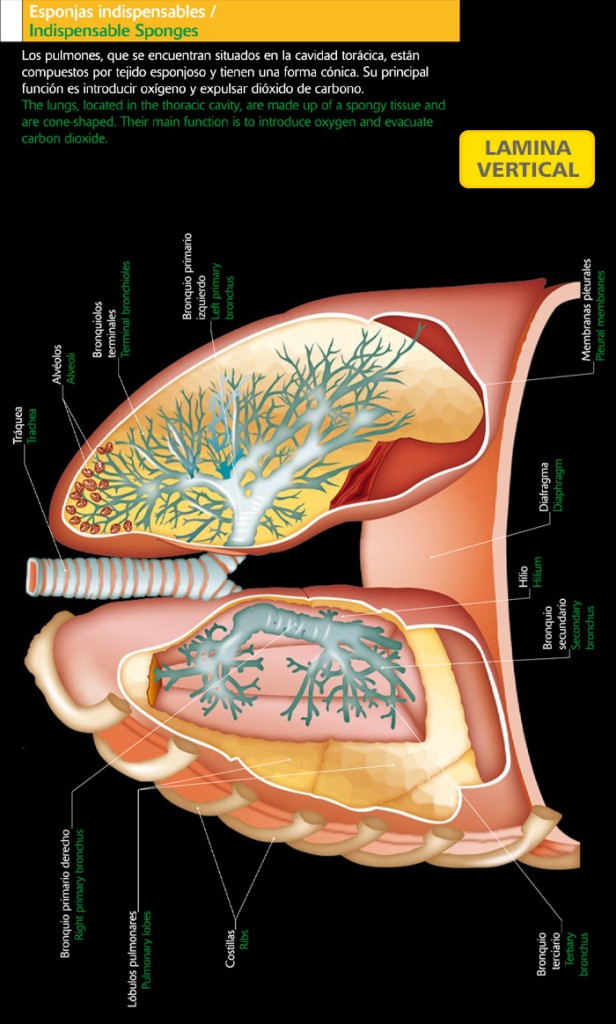

El Pulmón derecho presenta tres lóbulos y el izquierdo dos. Así, el Bronquio derecho se divide en 3 ramas principales, una para cada lóbulo antes de seguir subdividiéndose; mientras que el bronquio izquierdo se divide en dos ramas principales. Cuando los Bronquios más pequeños llegan a tener menos de 1 mm de diámetro, el cartílago desaparece y pasan a llamarse Bronquiolos, cuyas paredes están constituidas por músculos. Cada Bronquiolo al dividirse origina los conductos alveolares, los que a su vez desembocan en los Sacos Alveolares o Alveolos (Ver figura 4).

Figura 4: Alveolo del pulmón derecho

Zona de Intercambio: Pulmones

Corresponde específicamente al Alvéolo. En ellos ocurre el importante proceso llamado Hematosis, proceso por el cual la sangre traspasa al aire alveolar sus productos de excreción (representados por el Co2) y a la vez se aprovisiona de O2 para transportarlo a todo el organismo.

Anatomía:

El pulmón es un órgano par, de color rosagrisáceo, en los cuales el pulmón derecho presenta 3 lóbulos, por tanto, tres bronquios y el izquierdo presenta 2 lóbulos, porque la punta del corazón se encuentra inclinada hacia esa dirección, presentando dos bronquios). Tienen forma cónica y con propiedades elásticas, que se aloja en la cavidad torácica, dentro de la jaula ósea formada por las costillas. Su vértice sobrepasa levemente a las clavículas y su base descansa sobre el Diafragma.

Exteriormente los Pulmones están recubiertos por una membrana llamada Pleura, esta membrana presenta 2 hojas: La hoja que está pegada a la caja torácica que se llama Pleura Parietal y la que está adosada al órgano mismo se llama Pleura Visceral, entre ambas hay un espacio llamado Espacio Intrapleural (Ver figura 5).